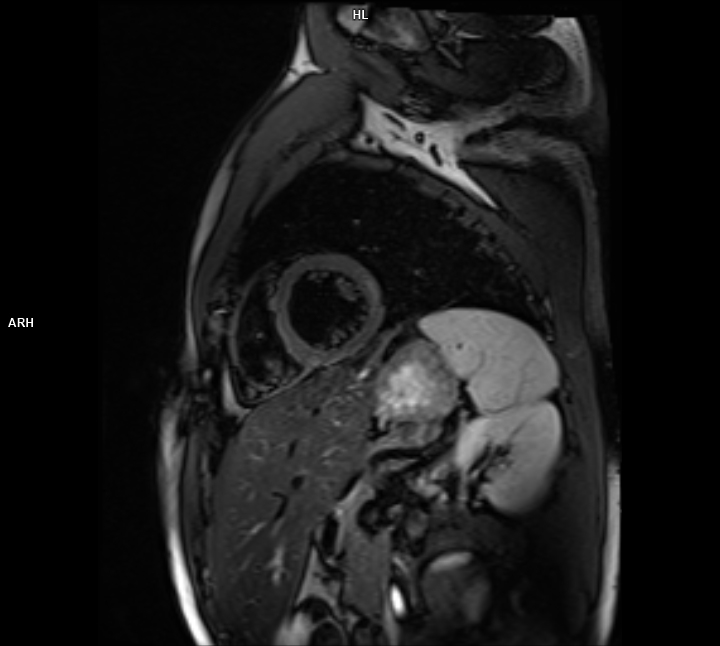

• 3 TESLA MR ÇEKİM GÖRÜNTÜLERİ

3 Tesla MR Çekim Görüntüleri

• 3 Tesla MR Çekim Görüntüleri